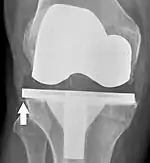

Overhang (arrow) does not seem to have any detrimental effect.[60]

Knee replacement is routinely evaluated by X-ray, including the following measures: